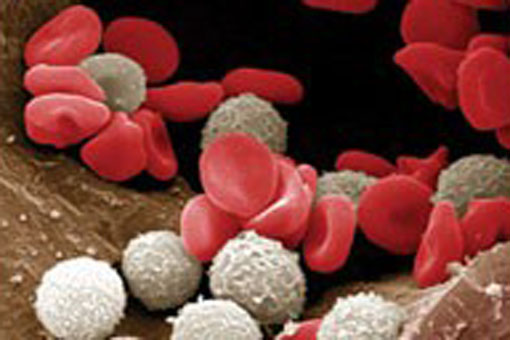

Grande successo della ricerca: un meccanismo che consente lo sviluppo di resistenza ai farmaci nella leucemia mieloide acuta (AML), portando così alla recidiva, è stato identificato da Kathy Borden dell’University of Montreal’s Institute for Research in Immunology and Cancer (IRIC) e dai suoi collaboratori. Kathy Borden è ricercatore presso l’ IRIC e professore al Dipartimento di Patologia e Biologia Cellulare.

Lo sviluppo di resistenza ai farmaci è uno dei principali problemi in oncologia clinica e la causa della recidiva in molti pazienti.

La nuova scoperta, recentemente pubblicata sulla prestigiosa rivista scientifica Nature, rappresenta un importante passo avanti nella lotta contro la leucemia mieloide acuta, una delle forme più letali di leucemia, perché suggerisce immediatamente strategie per superare la resistenza ai farmaci. Inoltre, il tipo di farmacoresistenza identificato è probabilmente implicato in altri tipi di cancro e un nuovo trattamento, sulla base di questi risultati, potrebbero avere vaste applicazioni nella cura del cancro.